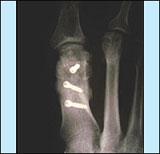

Subcapitale Verschiebeosteotomie nach Chevron

- V-förmige Korrektur und Verschiebung

des Mittelfußköpfchens, Stabilisierung mit Draht

oder Knochenschrauben (auch aus bioresorbierbarem Material)

- Vorteil: Dreidimensionale Korrektur,

Mittelfußköpfchen kann auch in seiner Höhe

korrigiert werden

- Bei guter Knochenqualität für

leichte bis mittlere Fehlstellungen